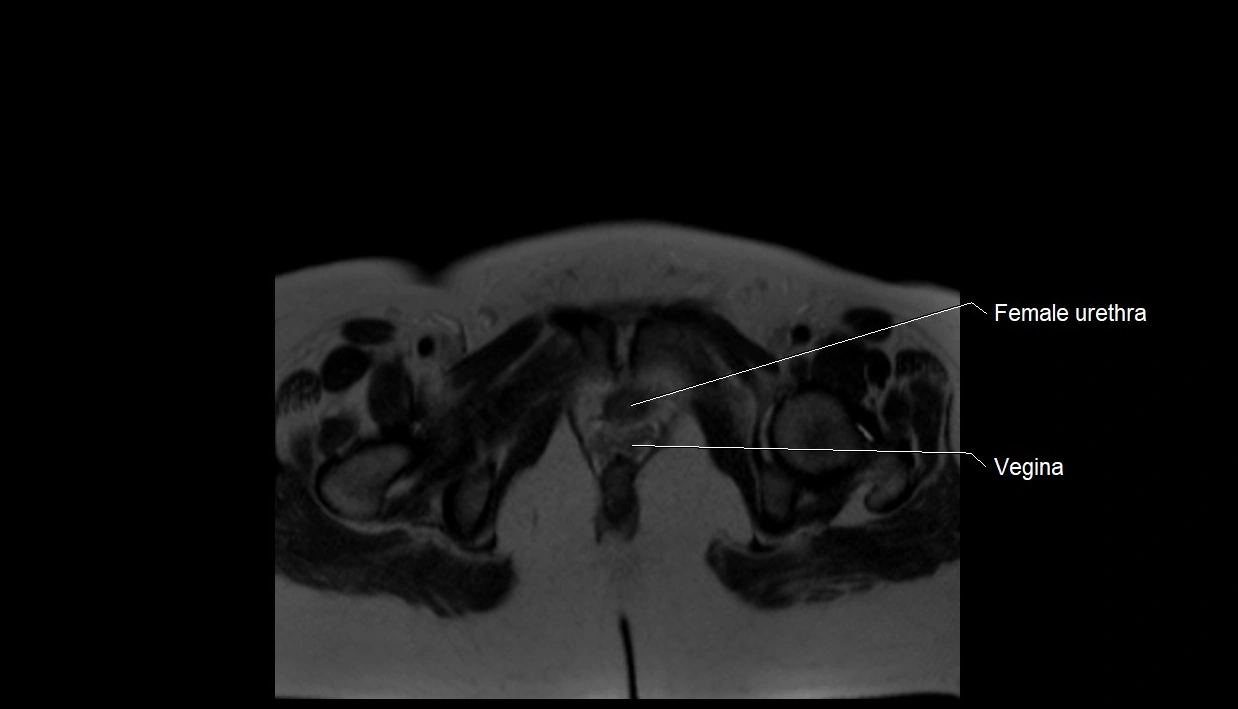

MRI Appearance

T2 HASTE (T2 GRE):

• Amniotic fluid shows very bright hyperintense signal

• Provides natural contrast against fetus and placenta

• Small particles (vernix) may appear as scattered hypointense foci within bright fluid

T1 GRE:

• Amniotic fluid shows low signal intensity (dark)

• Hemorrhage, infection, or proteinaceous content may cause focal or diffuse high signal intensity

MRI image

image